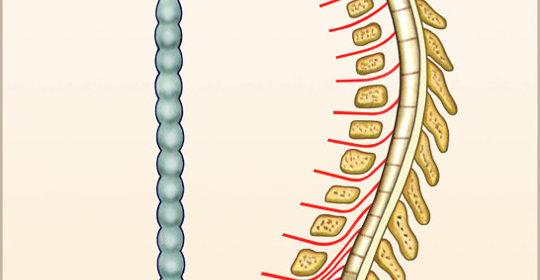

脊神經壓迫:背部的煎熬,症狀與科學疏導方法詳解